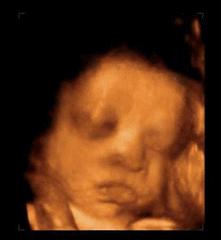

还有,妈妈要是生气了小家伙也能感受到,会跟妈妈一样发脾气。

不过发脾气前要先来一些预备动作:

伸展四肢,抬手活动肩部,准备完毕!

▼

看到小笼包大的拳头没有!我打!

呼!不行,还没解气,我的洪荒之力还没有发泄完,我踢!